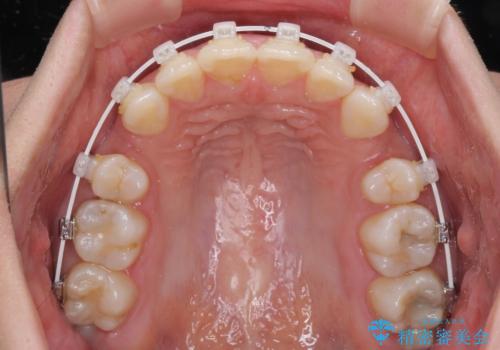

2年ほどインビザラインを使用しましたが、どうしても歯の移動がマウスピースに追随せず、全顎ワイヤー矯正へ切り替えました。

ワイヤー装着後は2年弱で、しっかりと仕上げることができました。